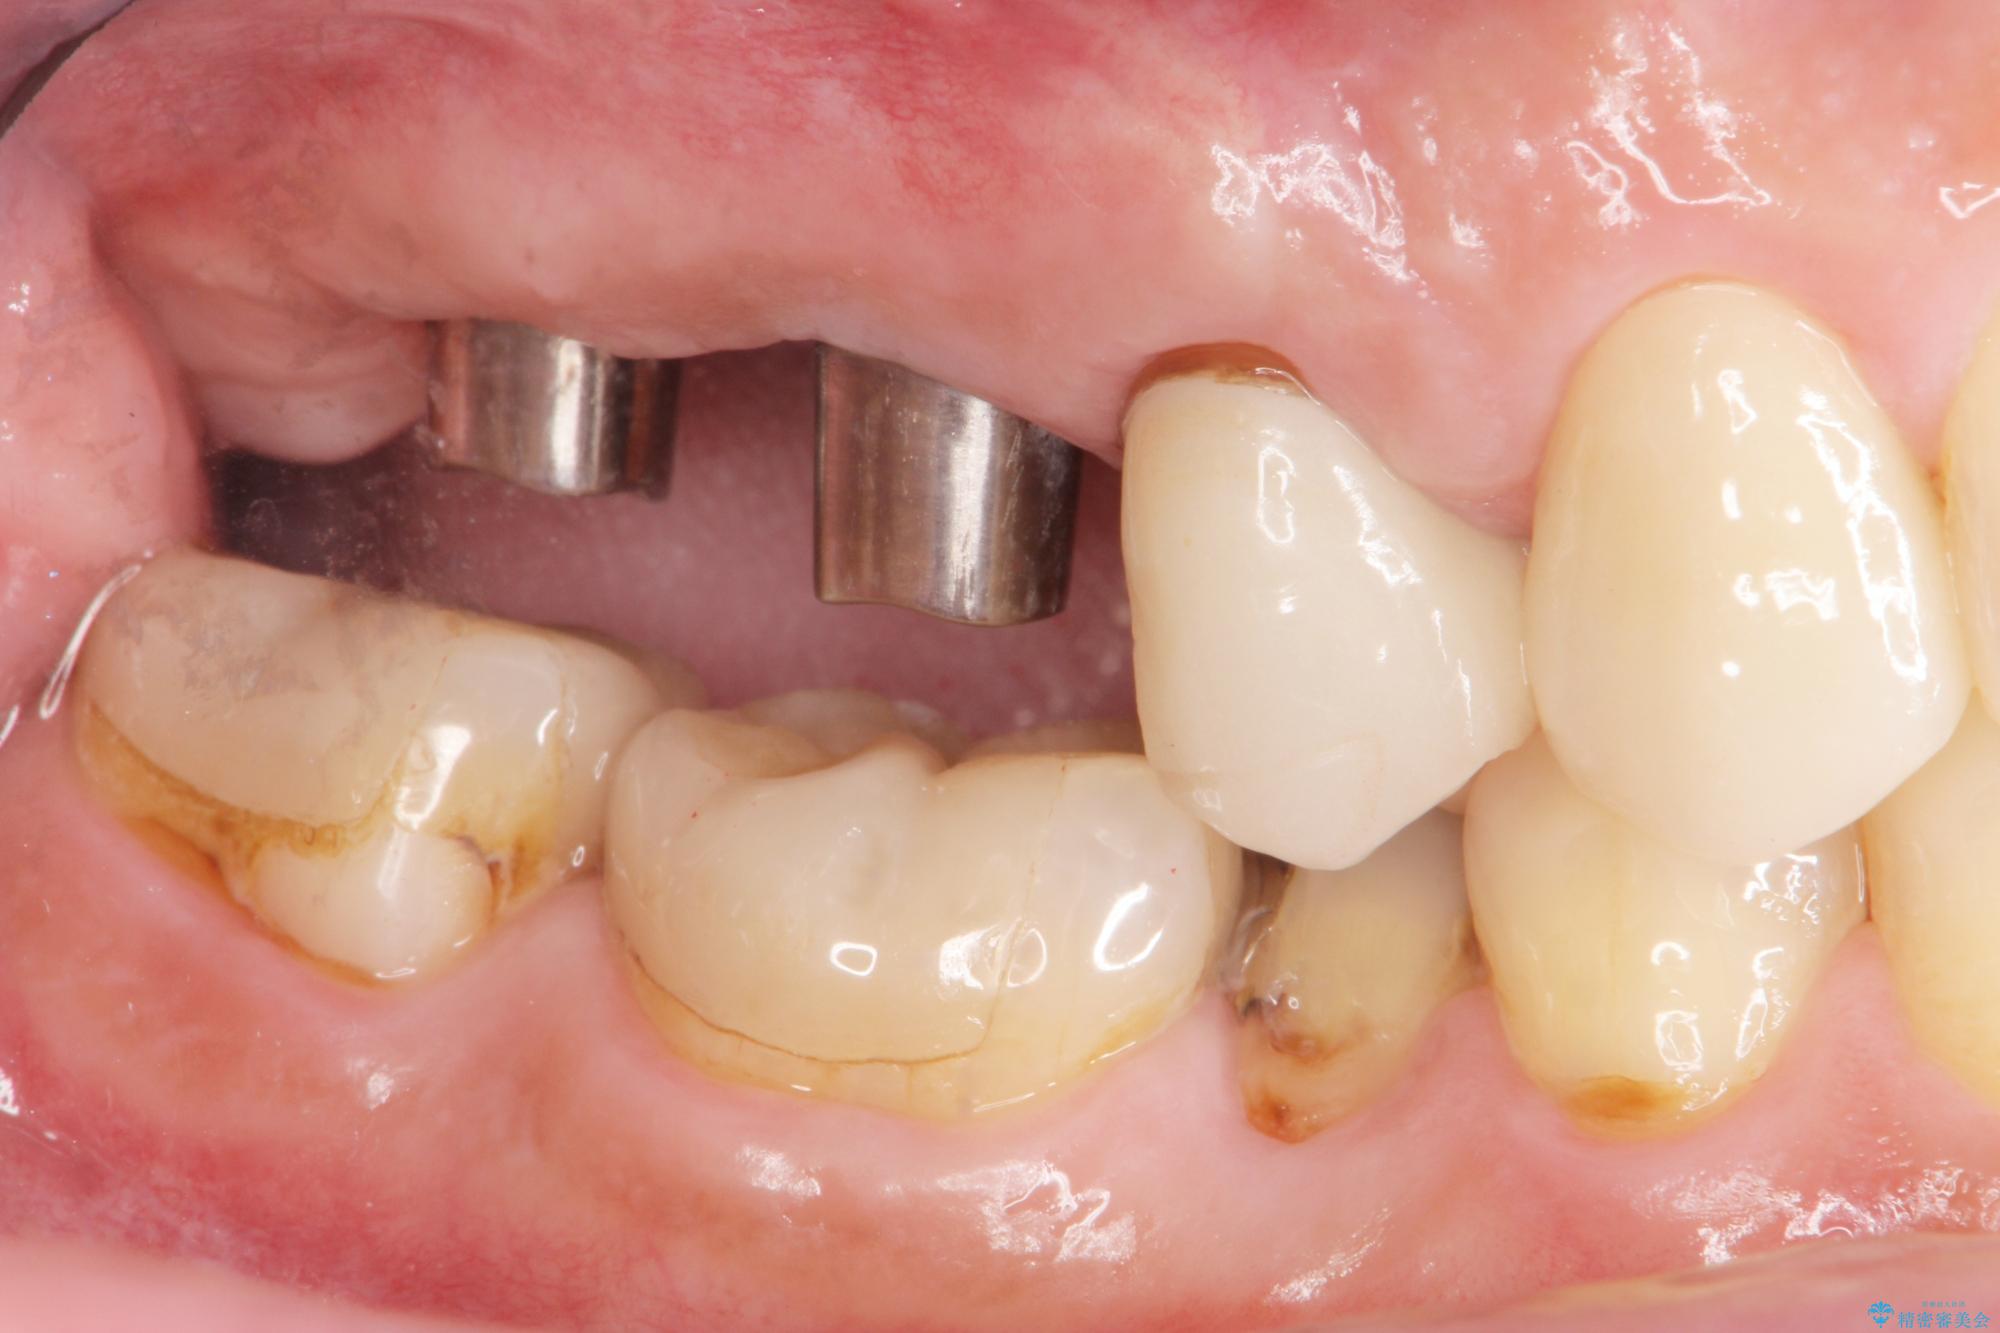

- 歯を抜いたまま放置してしまい、「やはりしっかりと噛めるような状態にしてほしい」とインプラント治療を希望され来院されました。

人工歯根であるインプラントを埋入することで奥歯でまたしっかりと噛める咬合機能を回復します。

- 88万円(インプラント×2・仮歯×2・チタンカスタムアバットメント×2・ジルコニアクラウン×2)費用は治療当時の料金となります